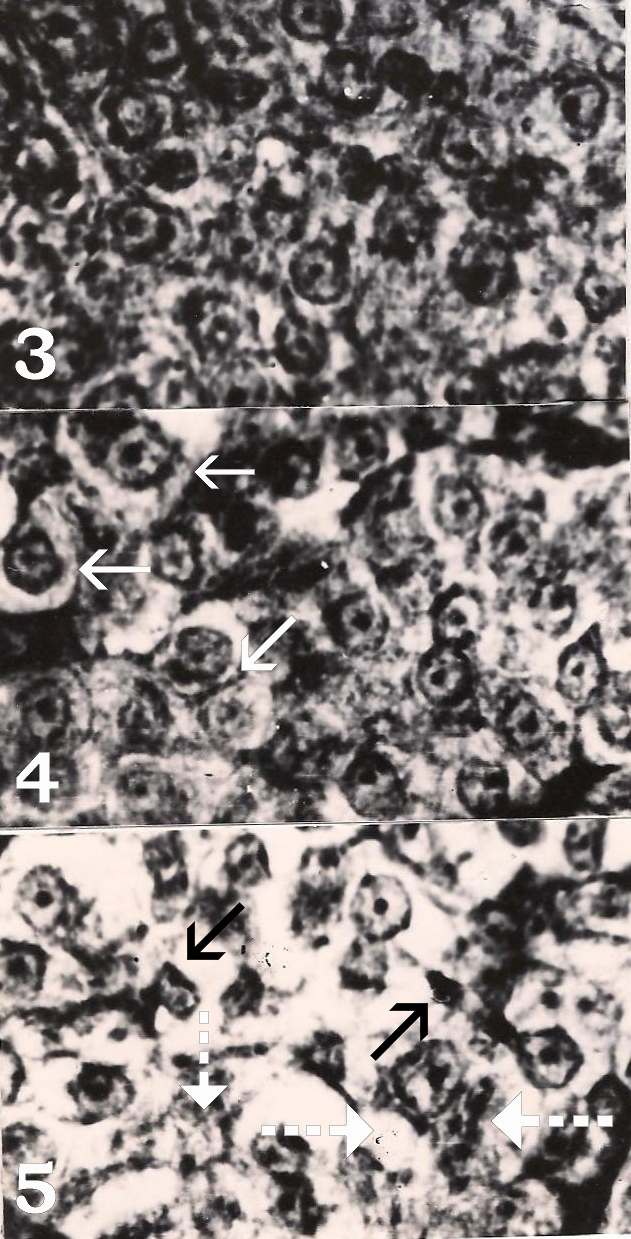

- Figure 5. Prolactin cells of 28 days chlorpyrifos exposed fish showing degeneration (arrows). Note vacuolization and cytolysis (white broken arrows) at some places. Herlant tetrachrome X 800.